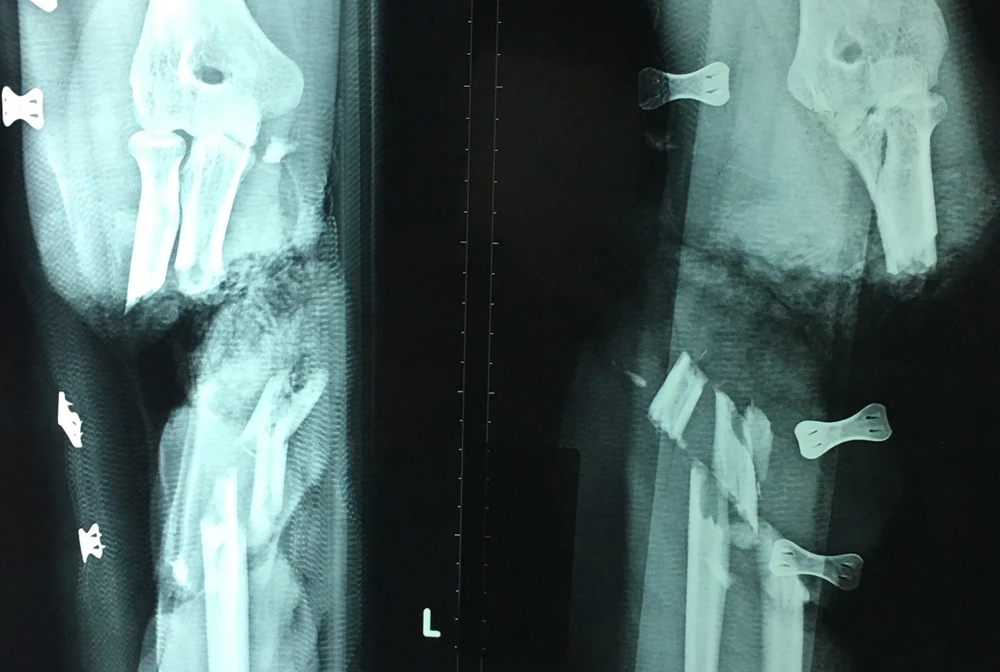

Kết quả chụp X quang cho thấy tay trái bệnh nhân bị lưỡi dao cắt đứt lìa. Ảnh: HÒA KHÁNH